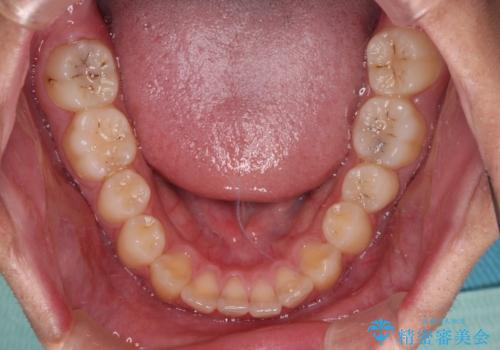

- 前歯のデコボコと隙間を気にして来院された高校生の患者様です。

下顎前歯が上顎前歯を突き上げるような咬み合わせとなっており、その影響で上顎正中に隙間ができている状態でした。

叢生の程度は軽度であり、本人もしっかりと使用する自信があるとのことだったので、インビザラインによる矯正治療を行うこととしました。

突き上げによる隙間を予防する為に、深い咬み合わせを改善するような治療計画としました。咬み合わせを改善させることはできましたが、隙間は後戻りしやすいので、通常の下顎前歯のみではなく、上顎前歯2本もワイヤーで保定を行いました。